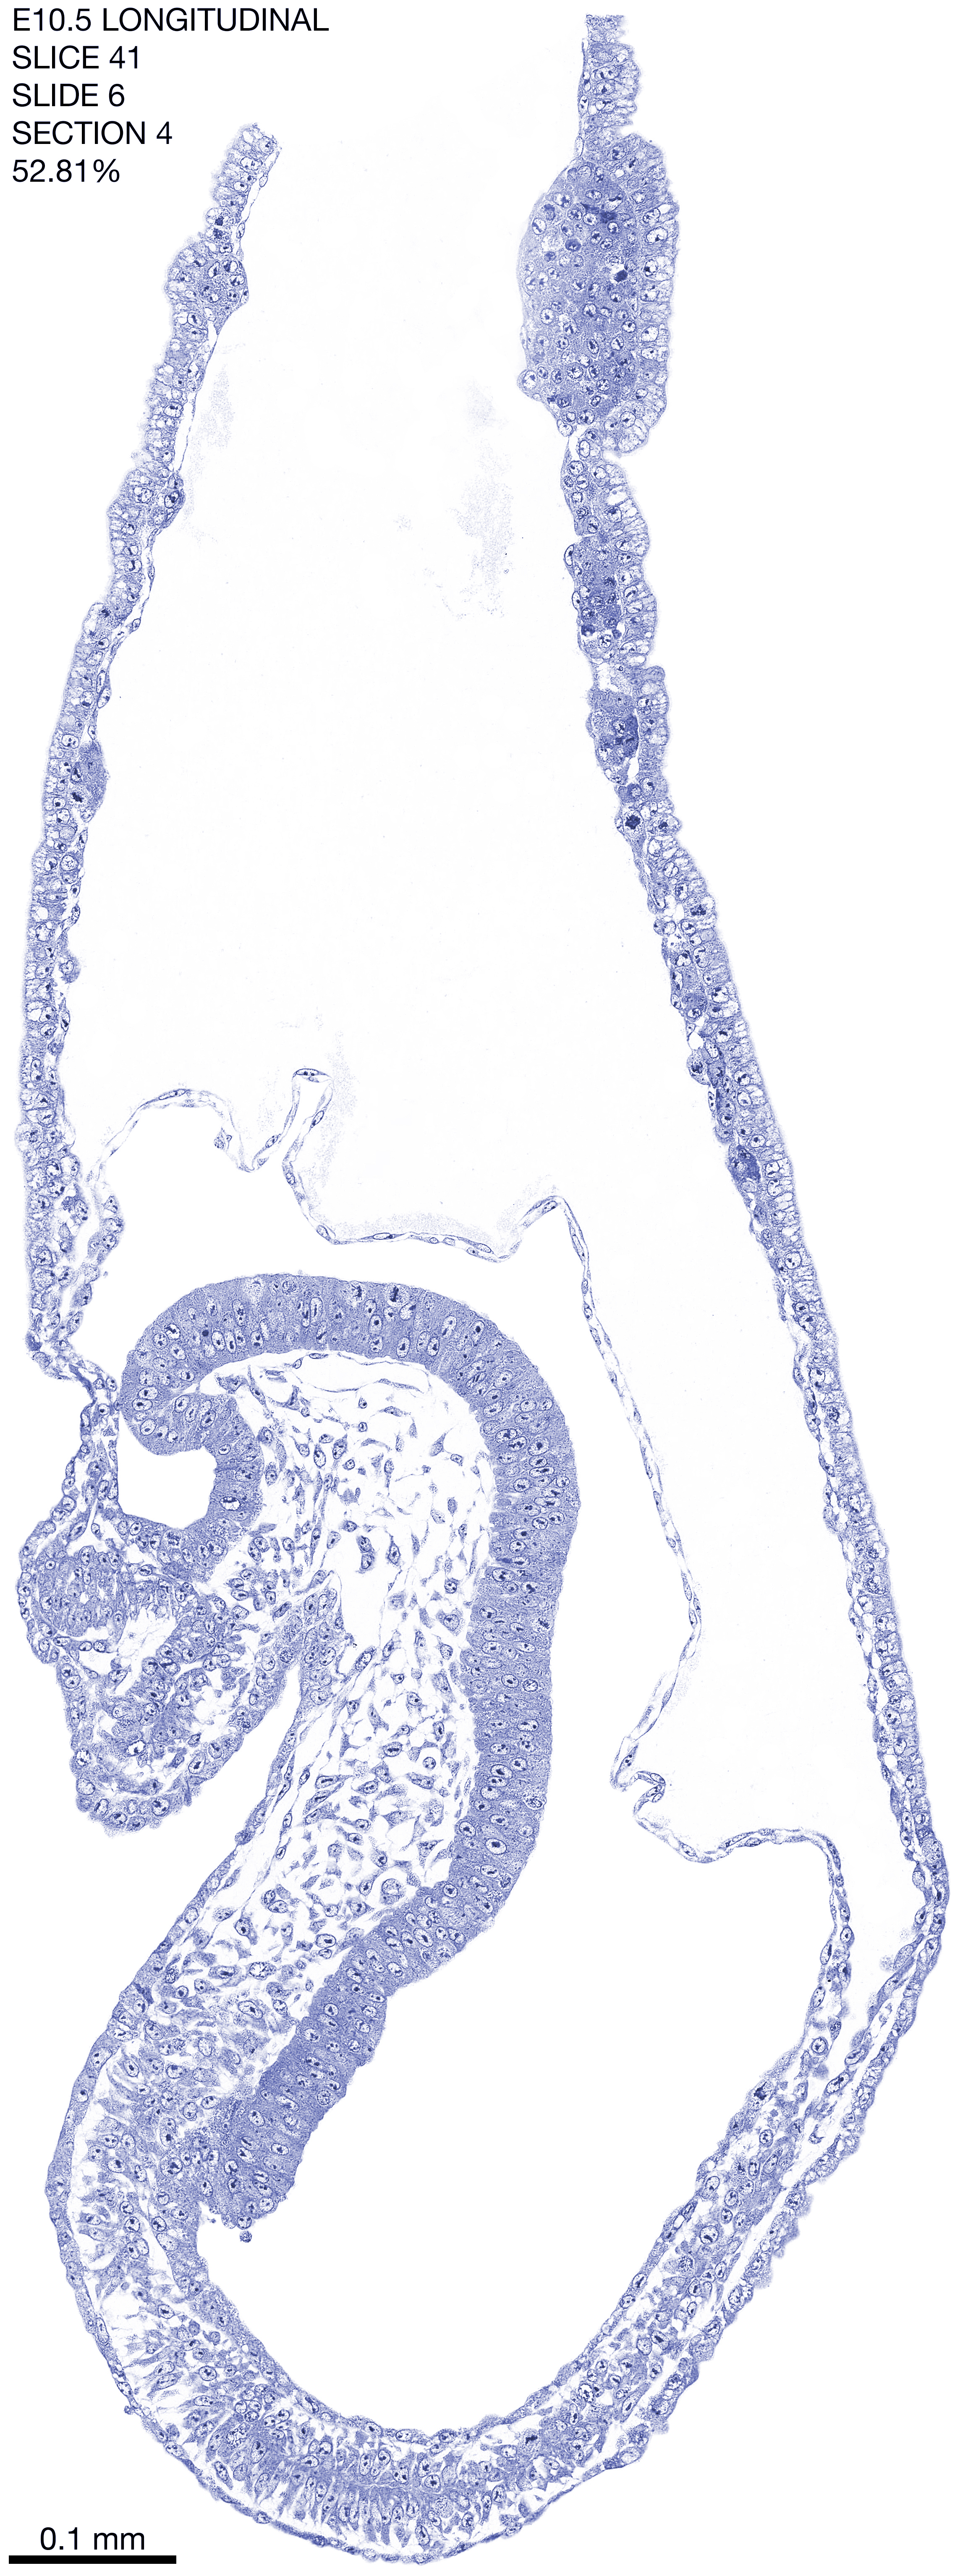

E10.5 Longitudianal Archive This page contains jpg files of ALL SLICES (each 3µm thick) that were scanned of the E10.5 longitudinally cut specimen. Download: Large | High Res Download: Large | High Res Download: Large | High Res Download: Large | High Res Download: Large | High Res Download: Large | High Res Download: Large | High Res Download: Large | High Res Download: Large | High Res Download: Large | High Res Download: Large | High Res Download: Large | High Res Download: Large | High Res Download: Large | High Res Download: Large | High Res Download: Large | High Res Download: Large | High Res Download: Large | High Res Download: Large | High Res Download: Large | High Res Download: Large | High Res Download: Large | High Res Download: Large | High Res Download: Large | High Res Download: Large | High Res Download: Large | High Res Download: Large | High Res Download: Large | High Res Download: Large | High Res Download: Large | High Res Download: Large | High Res Download: Large | High Res Download: Large | High Res Download: Large | High Res Download: Large | High Res Download: Large | High Res Download: Large | High Res Download: Large | High Res Download: Large | High Res Download: Large | High Res Download: Large | High Res Download: Large | High Res Download: Large | High Res Download: Large | High Res Download: Large | High Res Download: Large | High Res Download: Large | High Res Download: Large | High Res Download: Large | High Res Download: Large | High Res Download: Large | High Res Download: Large | High Res Download: Large | High Res Download: Large | High Res Download: Large | High Res Download: Large | High Res Download: Large | High Res Download: Large | High Res